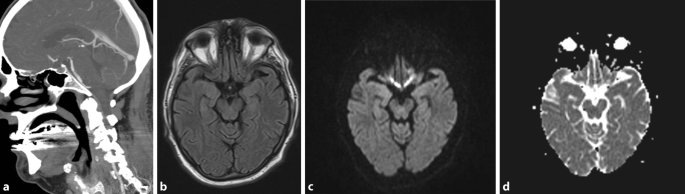

Stroke Mimics Kontrastmittelinduzierte Neurotoxizitat Als Seltene Ursache Springerlink

Stroke Mimics Kontrastmittelinduzierte Neurotoxizitat Als Seltene Ursache Springerlink from media.springernature.com